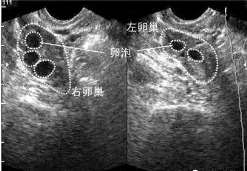

查看全文临床上导致输卵管堵塞的原因有很多,最主要的就是炎症,所以一旦出现下腹疼痛、白带异常等症状时,就要引起重视,及时 […]